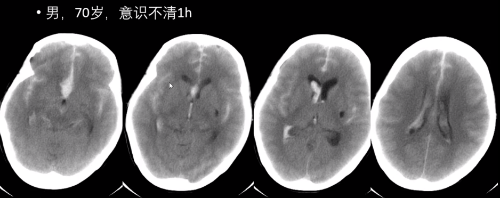

(2)Percheron 动脉梗死

发病机制为从一侧大脑后动脉 P1 段发出一条主干动脉(Percheron动脉)闭塞所致,该动脉分支供应双侧丘脑(如下图可见解剖学示意图)。

病因脑小血管病、心脏疾病、大动脉疾病等。

典型临床表现意识障碍、垂直注视麻痹、记忆力缺损三联征。

影像学表现:双侧丘脑、中脑长 T1 长 T2 信号;中脑“V”字征。